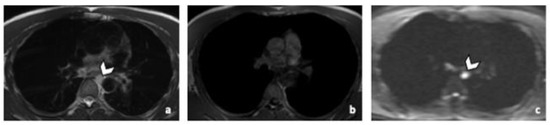

Figure 3.

False negative supra-diaphragmatic lymph node during the CT reading in a 28-year-old man with NSGCC. Axial T2-weighted image (a), coronal reformatted 3D T1 GRE Fat Sat (c) and high b-value DWI (inverted greyscale, b = 1000 s/mm2) MR images of the whole body (d) and axial CT image after intravenous injection of iodinated contrast agent (b). The enlarged left supra-clavicular lymph node (arrowhead) was identified by both readers during the MRI readings; it was missed by both readers during the CT readings. Abbreviations: NSGCC: Non-Seminomatous Germ Cell Cancer, 3D: Three Dimensional, T1 GRE: T1 Gradient Echo, DWI: Diffusion Weighted Imaging, MRI: Magnetic Resonance Imaging, CT: Computed Tomography.